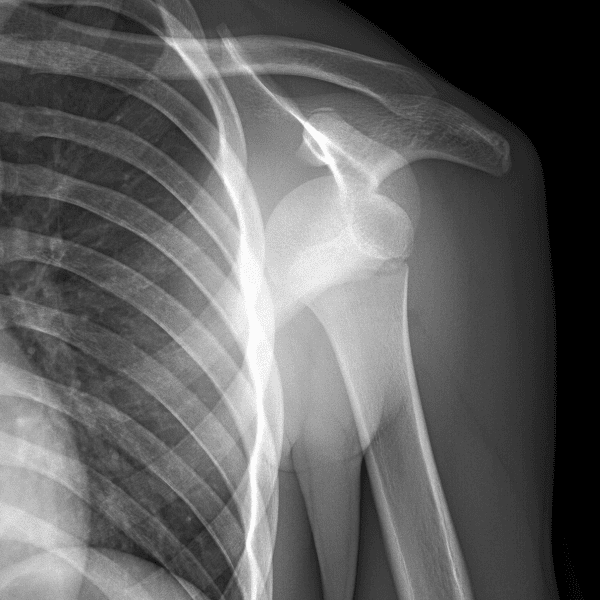

Simuliert den Dienst durch subtile oder schwierige Fälle und einige Normalbefunde.

30 Fälle